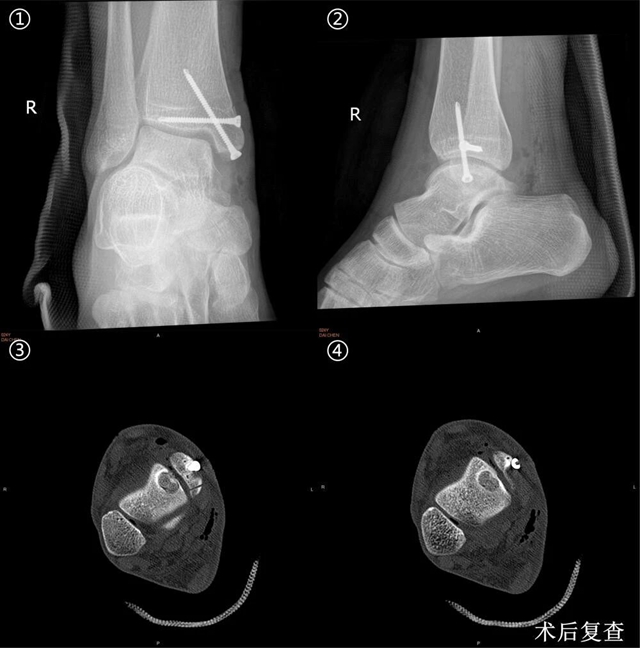

经仔细查体并完善相关检查后,诊断其为“右踝关节距骨骨软骨损伤”,鉴于病情反复,软骨损伤面积较大,建议住院手术治疗。

在科室副主任关钛元教授组织专家经过认真讨论后,认为其软骨损伤面积超过120m㎡,损伤深度超过12mm,并且伴软骨下骨囊肿形成,分型为Hepple V型,保守治疗及微骨折术治疗疗效有限,后期可能发展为创伤性踝关节炎,张磊教授建议行“踝关节镜检清理+新型半斜型内踝截骨+取同侧膝关节软骨行马赛克软骨移植术。”